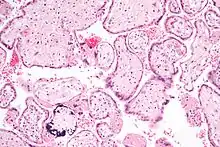

Micrograph of CMV placentitis

Micrograph of CMV placentitis A 3D Power Doppler image of vasculature in 20-week placenta